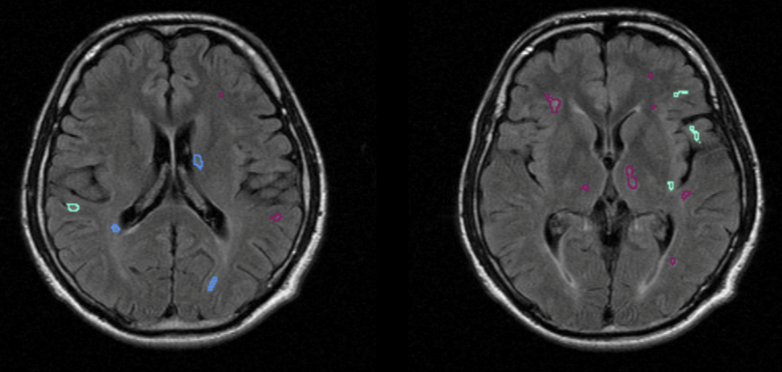

Embedding AI for clinical and operational efficiencies helps better manage high volumes of patient data and enables large-scale screening programs, not only for cancer detection, but also other image-based population health efforts. DeepHealth is unlocking the value of imaging to address a range of diseases, including assessment and monitoring of neurodegenerative diseases.